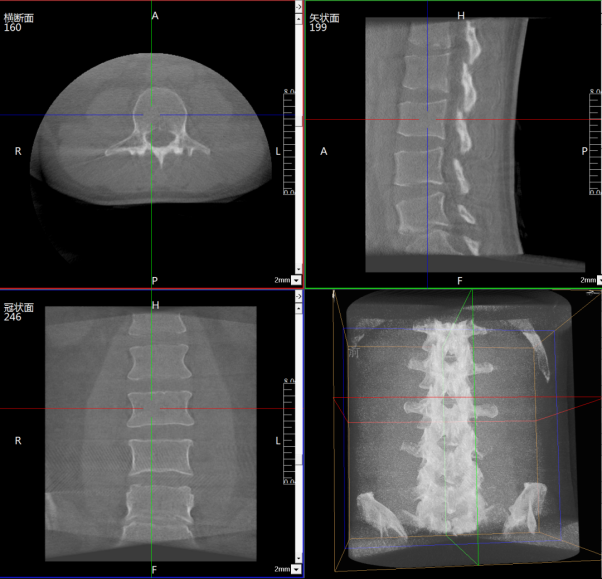

Spinal surgeries in pain management focus on neuromodulation, requiring precise planning of the puncture path while carefully avoiding blood vessels, nerve roots, and visceral structures.Given the complex anatomy of nerves and blood vessels surrounding the spine, the inherent superimposition of structures in conventional 2D imaging may cause misinterpretation.

The 3D C-arm can generate intraoperative three-dimensional spinal images and CT-like cross-sectional views, providing physicians with a more comprehensive perspective for observation and clinical diagnosis.